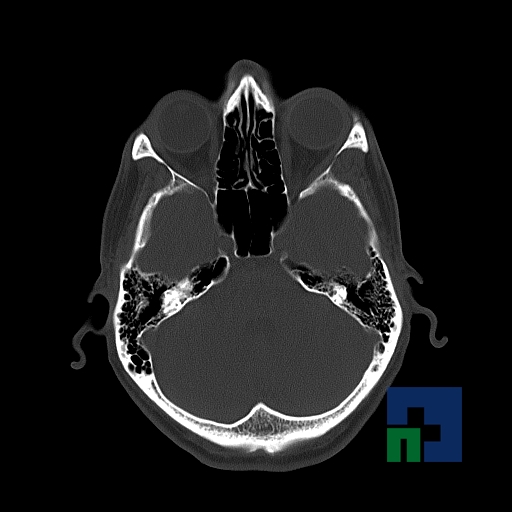

În cazul traumatismelor cranio-cerebrale:

- Diagnosticul edemului cerebral, a contuziei cerebrale, a leziunilor axonale difuze edematoase/hemoragice, a dilacerării cerebrale, a hematomului intraparenchimatos posttraumatic, a hematoamelor subdurale/extradurale (acute, subacute, cronice), a hemoragiei intraventriculare, a hemoragiei subarahnoidiene

- Diagnosticul traumatismelor de bază de craniu

- Diagnosticul fracturilor: